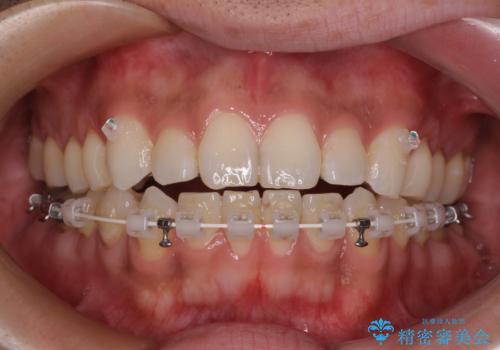

- 矯正装置

- ハーフリンガル

自己管理の大変なインビザラインや、目立つ表側のワイヤー矯正は避けたいとのことで、

上顎だけ裏側装置のハーフリンガルにて矯正しました。